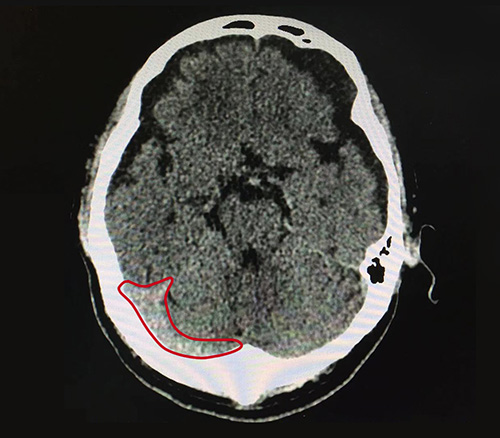

10月17日,為了進一步治療,唐叔叔在老伴的陪同下就診于藍十字腦科醫(yī)院,接診的是神經(jīng)內(nèi)科7A病區(qū)主任張靜波,張主任在了解了唐叔叔具體病情和癥狀后,為了更準(zhǔn)確的確定病癥,建議其行頭顱CT,結(jié)果顯示:1、蛛網(wǎng)膜下腔出血(外傷性);2、腔隙性腦梗死;3、腦挫裂傷(右額葉);4、雙側(cè)額顳部硬膜下積液;5、枕骨骨折。

▲患者當(dāng)時右側(cè)顳部蛛網(wǎng)膜下腔出血比較嚴(yán)重